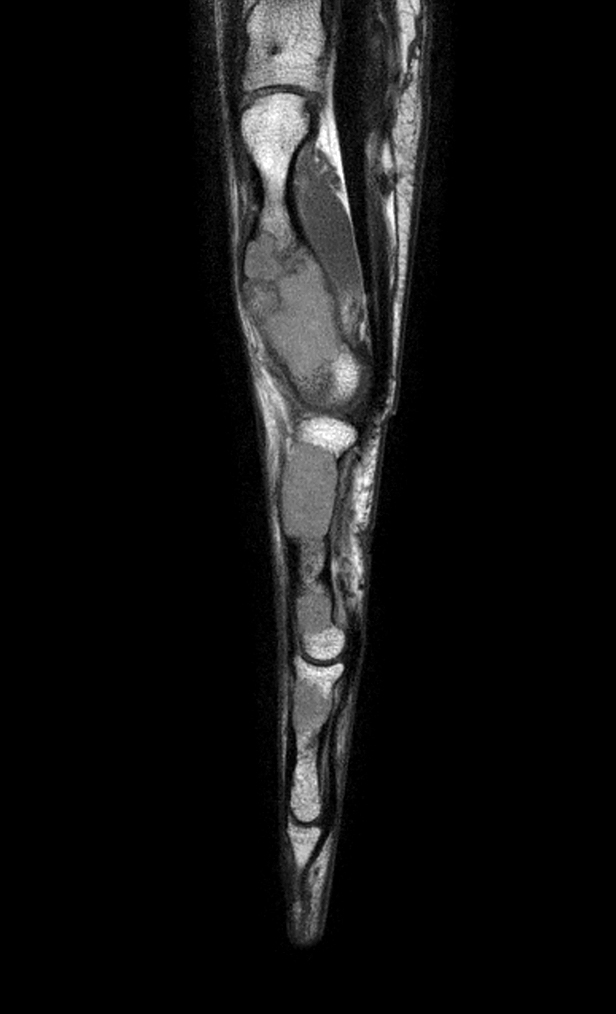

Sagittal T1w mDIXON XD TSE (Water only)

Sagittal T1w mDIXON XD TSE (In Phase)

Sagittal T1w mDIXON XD TSE (Partial FatSat)